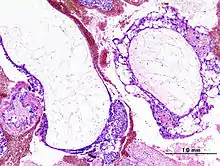

| Histopathologic image of hydatidiform mole (complete type). H&E stain. | |